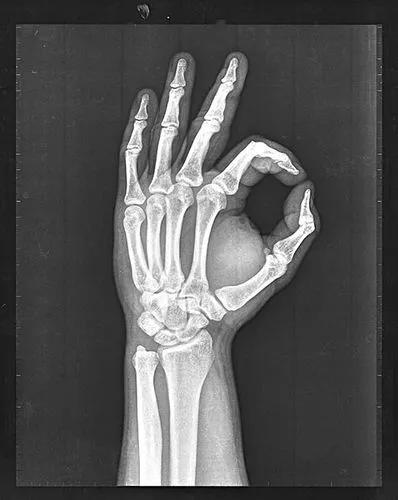

無比的亢奮中,倫琴第一時間讓妻子來到實驗室,並拍下人類的第一張手的骨骼照。這宛如“上帝之手”的直觀骨骼構造,嚇壞了倫琴的妻子。她從此拒絕再進入倫琴的實驗室。

倫琴的妻子手持熒光板由近向遠逐漸移動,而倫琴則拍下了自己妻子的手掌,這是人類歷史上最早的一張“X光片”,上面還戴着一枚象徵着愛情的結婚戒指。而這隻手宛如一隻上帝之手,爲人類打開了一扇新的大門,醫學影像學的大門。而倫琴太太則因爲驚嚇過度,從此拒絕進入倫琴的實驗室。